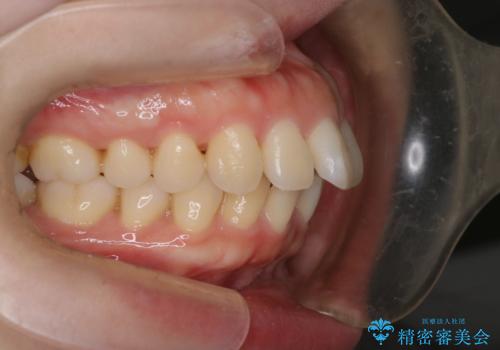

【審美装置】癒合歯がある方の治療

- 前歯の前突を主訴に来院されました。

下の前歯は癒合歯がある珍しいケースです。

治療に関しては小臼歯を4本抜歯して前歯を下げるような計画を立てて治療しました。